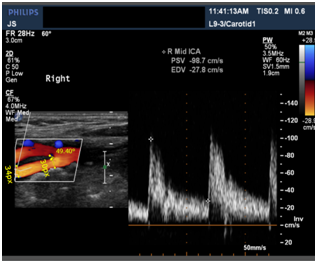

PSV is the Peak Systolic Velocity obtained from the Dicom images and considered as real part of the peak to peak value in the above graph similar to the denominator of ‘amp’. Here after, we mention only the PSV values.

Similar to the above ultrasound image, 5 images at different points in CCA, ICA, and ECA respectively of the same patient were taken. And velocities at the points L2, L5 and L3 were calculated given velocities at L1 and L4 with ±5% errors based on the flow rate division with different Windkessel models stitched along the artery with the calculated radius from the images and assuming an average elasticity, thickness, viscosities and densities of the blood (Figure 7).

Table 1 Compares the velocities obtained by Simulation (Est. velocity) and the observed velocities from Ultrasound image of CCA

These tables shows the simulated results of a patient.